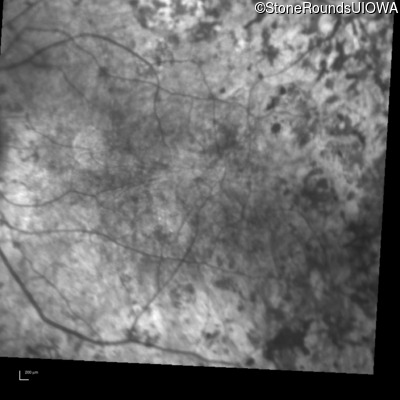

Infrared Fundus Photograph - Right - 20/150

Exemplar

Infrared Fundus Photograph - Left - Light Perception